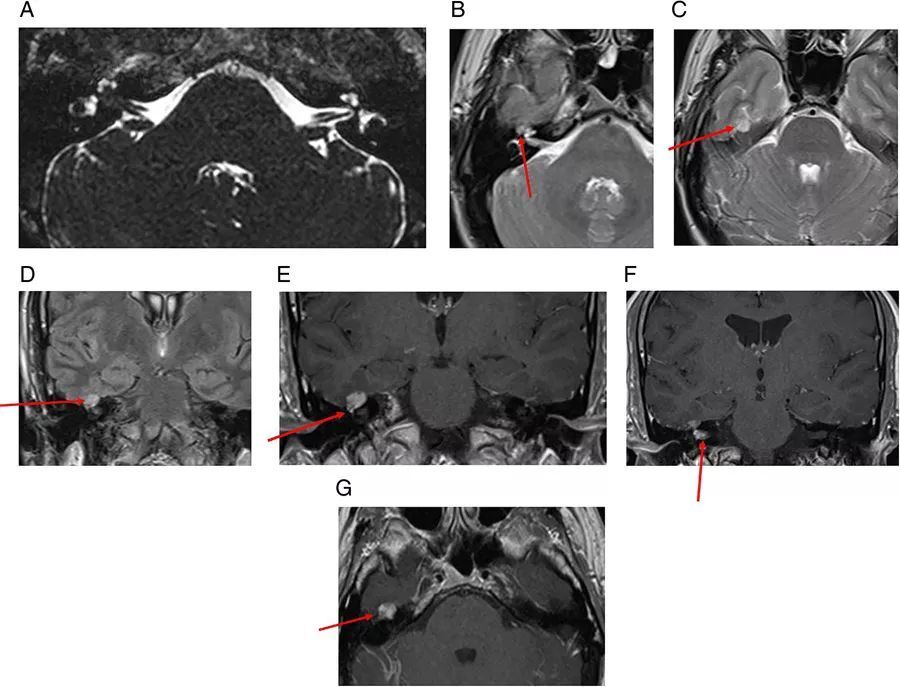

图6  左侧桥小脑角区表皮样囊肿。病灶呈T1低信号、T2高信号,DWI上弥散受限,延伸至Meckel氏腔,左侧小脑中脚和第四脑室受压,三叉神经、面神经、听神经也被压缩

图7  蛛网膜囊肿。可见右侧桥小脑角区呈脑脊液信号的不规则肿物,右侧小脑半球受压变形

图8  双侧桥小脑角区脂肪瘤。T1WI上呈现高信号,压脂像上则无信号。如果只根据增强扫描的图像(E和F),很容易将脂肪瘤误认为前庭神经鞘瘤或脑膜瘤

图9  乳腺癌所致恶性脑膜炎。可见左侧内听道强化肿物,类似于前庭神经鞘瘤,桥脑池中另可见一肿物,沿着左三叉神经的走行路径延伸